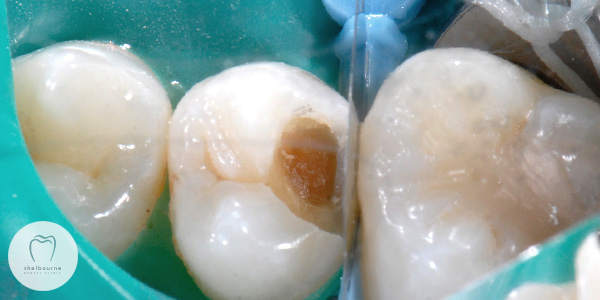

I need to get this sorted out quickly. This next photo shows the actual decay beneath the surface of the tooth. Brown, sticky and mushy….uugghhh!

Looks nasty doesn’t it?